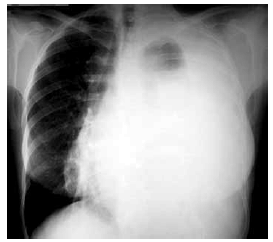

Mulher de 27 anos de idade apresenta quadro de dispneia progressiva há 2 meses, associado a tosse seca, dor torácica, sudorese noturna e perda de peso. Ao exame físico: PA: 112 x 74 mmHg, FC: 108 bpm, FR: 24 ipm e SatO2: 89%; adenomegalias cervicais; abdome e membros inferiores: sem alterações. A radiografia de tórax feita é mostrada a seguir. Uma toracocentese é realizada, com os seguintes achados: células: 5 260/mm3, (95% de linfócitos); proteínas totais: 3,9 g/dL; desidrogenase lática: 2 820 U/L; pH: 7,37; glicose: 72 mg/dL; adenosina deaminase: 18 U/L.

Com os dados descritos, o diagnóstico mais provável é